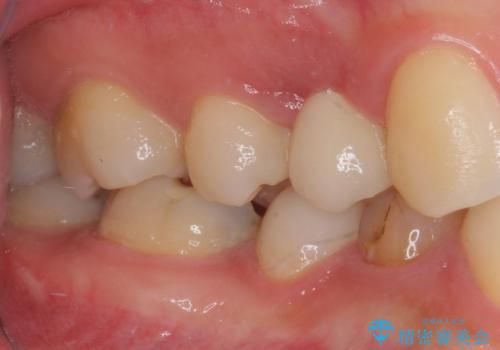

口を開けたときに目に付く領域であったので、ジルコニアカスタムアバットメントを用いたインプラント治療を行うこととしました。

ジルコニアカスタムアバットメントは、歯肉ラインに金属が見えにくいというだけでなく、クラウンを装着する土台の形が天然歯と近い形態となるため、清掃性が高く歯肉が腫れにくいというメリットがあります。

インプラントは、人工骨を用いた際の骨誘導能が比較的高いとさせるストローマン社のSLActiveを使用しました。